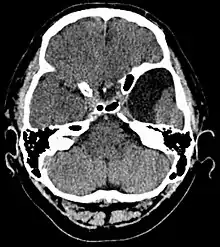

| Arachnoid cyst | |

Diagnosis is principally by MRI. Frequently, arachnoid cysts are incidental findings on MRI scans performed for other clinical reasons. In practice, diagnosis of symptomatic arachnoid cysts requires symptoms to be present, and many with the disorder never develop symptoms.